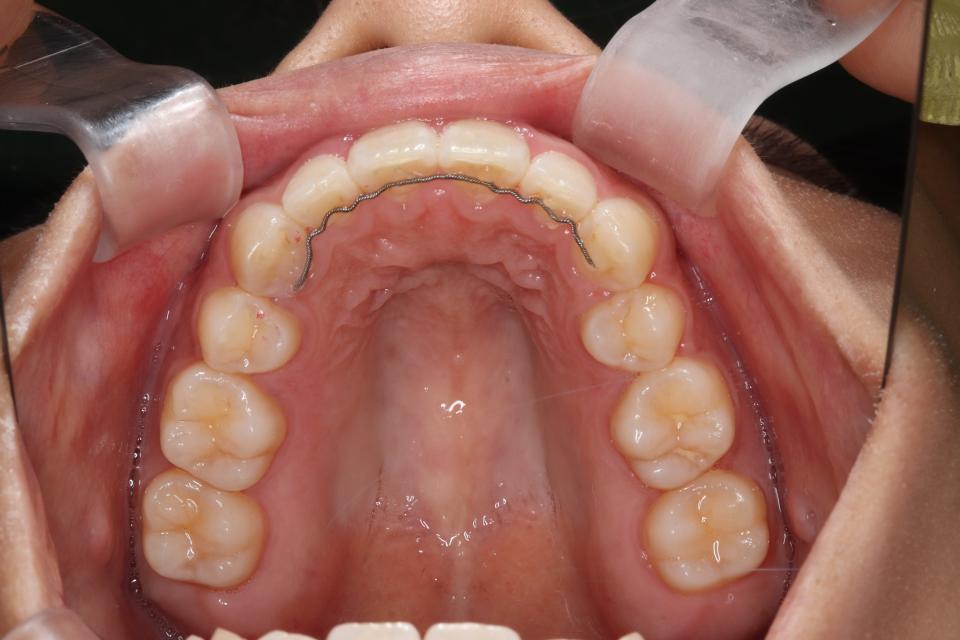

矯正治療後

マウスピース型の矯正治療装置を使用し、前歯の歯並びのみの改善を行いました。

現在は保定装置を使用し定期的にチェックしています。